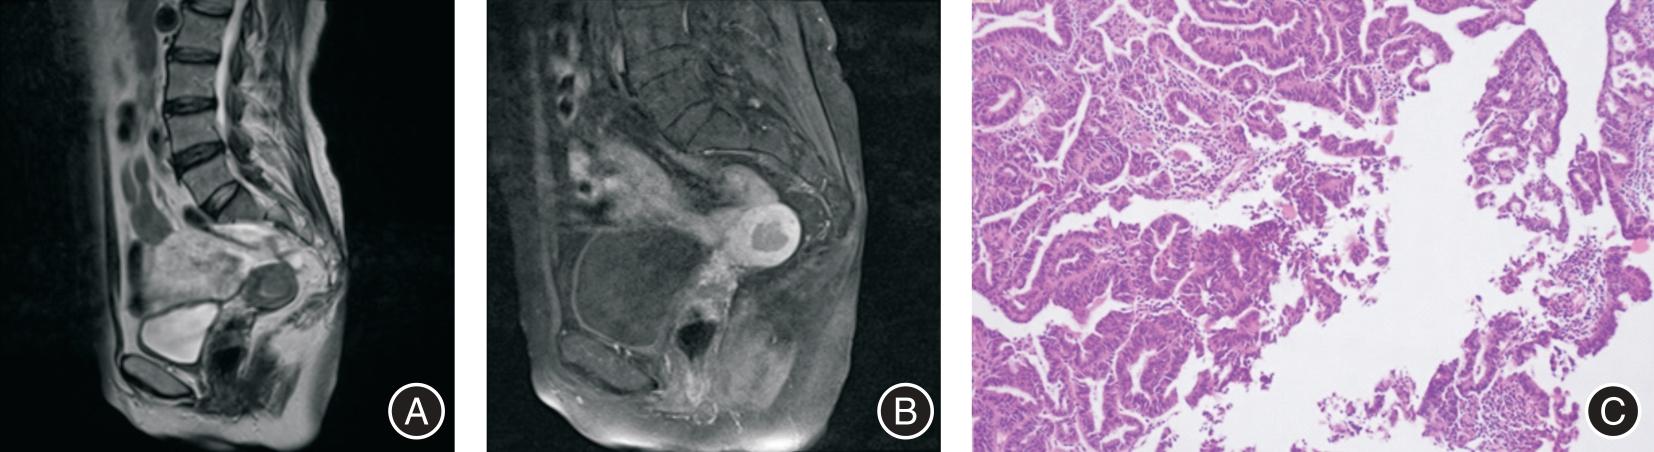

目的 探讨子宫内膜癌(EC)肿瘤体积与子宫体积比值(N/U)联合肿瘤表观扩散系数(ADC)值对EC病理分级的预测价值。 方法 回顾性分析2020年7月至2023年1月收治的107例EC患者的资料,所有患者术前均进行了磁共振(MRI)检查,将病理学诊断作为金标准。将低分化患者纳入高级别组,中、高分化纳入低级别组。分析影响EC患者病理分级的因素,分析MRI指标预测EC患者病理分级的价值。 结果 手术病理检测显示高级别患者24例,低级别患者83例。Logistic多因素回归分析显示:N/U、ADC、rADC闭孔内肌是影响EC患者病理分级的因素( P < 0.05)。ROC曲线结果显示,N/U、ADC、rADC闭孔内肌及三者联合预测EC患者病理分级的灵敏度分别为70.83%、75.00%、79.17%、83.33%,特异度分别为71.08%、79.52%、78.31%、85.54%,AUC分别为0.734、0.756、0.741、0.891。 结论 N/U、ADC、rADC闭孔内肌三者联合预测EC患者术前病理分级效能良好。

Objective To investigate the value of tumor volume to uterine volume ratio (N/U) combined with tumor apparent diffusion coefficient (ADC) in predicting the pathological grade of endometrial carcinoma (EC). Methods Data of 107 patients with EC admitted from July 2020 to January 2023 were retrospectively analyzed. All patients underwent preoperative magnetic resonance imaging (MRI), and pathological diagnosis was used as the gold standard. Patients with low differentiation were included in the high grade group, and patients with medium and high differentiation were included in the low grade group. The factors affecting the pathological grading of EC patients were analyzed, and the value of MRI index in predicting the pathological grading of EC patients was analyzed. Results The pathological examination showed that there were 24 high-grade patients and 83 low-grade patients.. Logistic multivariate regression analysis showed that N/U, ADC, rADC internal obturator muscle were factors affecting the pathological grade of EC patients ( P < 0.05). ROC curve results showed that the sensitivity of N/U, ADC, rADC internus obturator muscle and their combination to predict the pathological grading of EC patients were 70.83%, 75.00%, 79.17%, 83.33%, the specificity were 71.08%, 79.52%, 78.31%, 85.54%, and the AUC were 0.734, 0.756, 0.741 and 0.891. Conclusion The combination of N/U, ADC, rADC and obturator internal muscle was effective in predicting the preoperative pathological grading of EC patients.